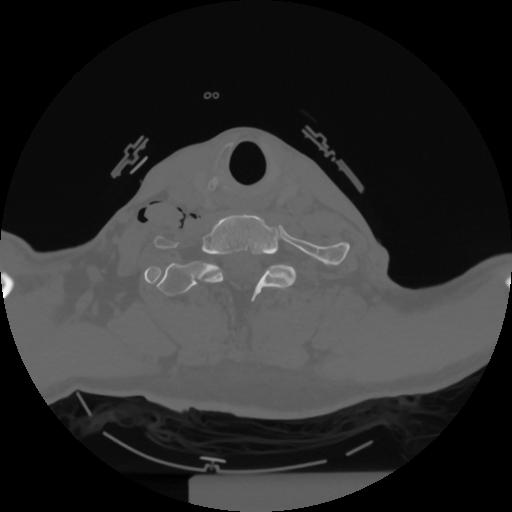

12 P.BLANDAS,,Vol,0.5,P.BLANDAS,,